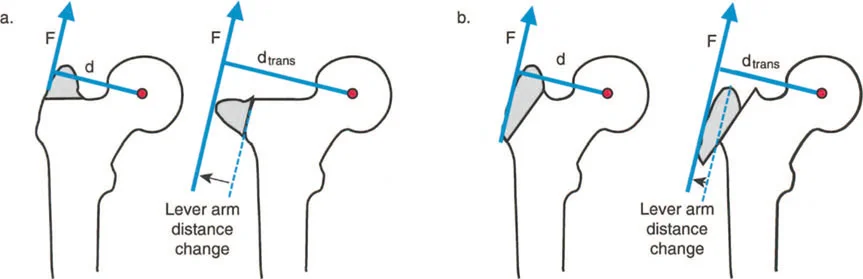

أمثلة أخرى رئيسية للتشوهات الديناميكية تشمل "الورم الفخذي المفرط" (Severe Femoral Anteversion) و "الورك الأفحج" (Coxa Vara). في كلتا هاتين الشذوذات المعمارية، يتم تقصير الطول الفيزيائي لذراع الرافعة لعضلات المبعدة (Abductor muscles) بشكل مرضي بسبب التشوه العظمي نفسه. قد تكون عضلة الألوية الوسطى (Gluteus Medius) صحية تمامًا، ومعصبة جيدًا، وقادرة على توليد قوة بيولوجية طبيعية، لكنها تعاني من خلل وظيفي سريري عميق لأن ميزتها الميكانيكية قد سُلبت بسبب الهندسة الهيكلية المتغيرة. هذه الفئة الفرعية المحددة من الأمراض تُعرف باسم "تشوه في طول ذراع الرافعة".

بشكل خاص، يصف خلل وظيفة الذراع الرافعة حالة سريرية تتشوه فيها أذرع الرافعة الداخلية و/أو الخارجية بسبب سوء محاذاة العظام، أو التشوهات الالتوائية، أو تيبسات المفاصل الموضعية.

بينما لا يستطيع الطب الحديث فعل الكثير لزيادة القوة البيولوجية الخام التي تولدها العضلة بشكل دائم (بخلاف العلاج الطبيعي)، يمكن غالبًا زيادة حجم العزم المؤثر على المفصل بشكل كبير ببساطة عن طريق تصحيح خلل وظيفة الذراع الرافعة جراحيًا. هذا هو جوهر النهج الذي يتبعه الأستاذ الدكتور محمد هطيف في علاج التشوهات العظمية المعقدة، حيث يركز على استعادة الميكانيكا الحيوية السليمة للجسم.

- الورك الأفحج (Coxa Vara): تشوه خلقي أو تطوري في عظم الفخذ يؤدي إلى تقصير ذراع الرافعة لعضلات الورك المبعدة، مما يضعف قدرتها على تثبيت الحوض.